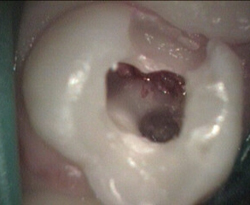

Primary first molar deep cavity pulp exposure pulp cleaning process

pulpotomy complete and lasered clean white filling being added

Restored